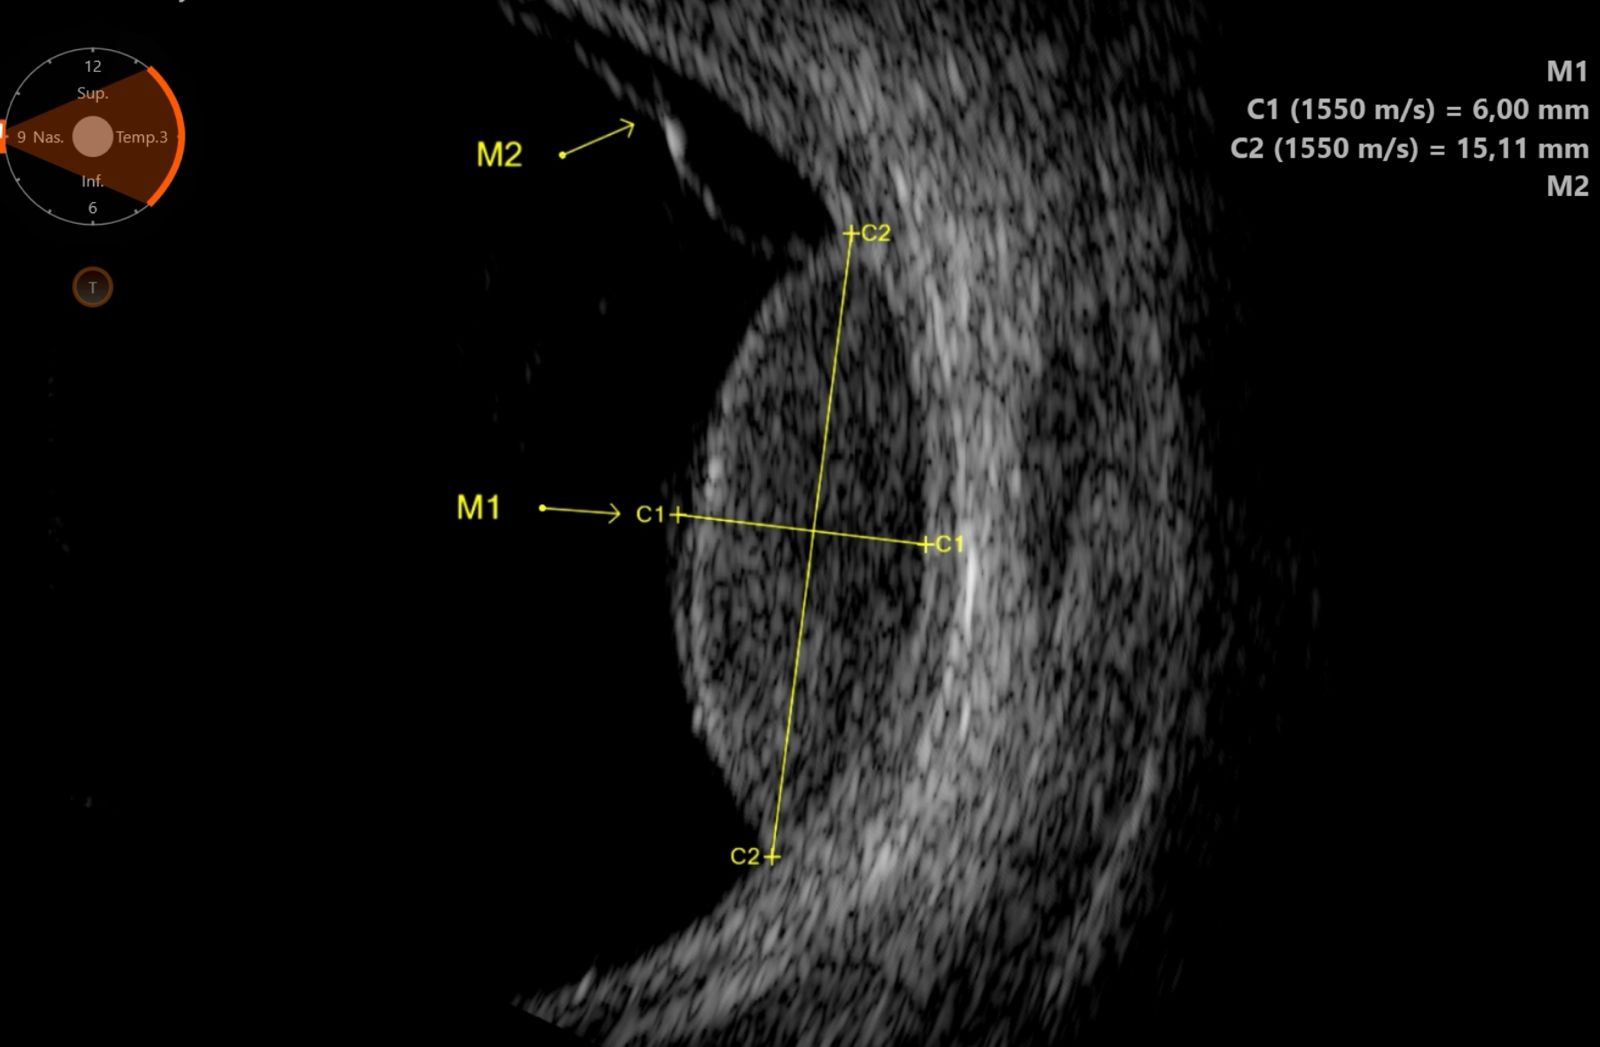

UBM — Biomicroscopie ultrasonore

La biomicroscopie ultrasonore (UBM) utilise des fréquences très élevées de 35 à 50 MHz, offrant une résolution exceptionnelle de 25 à 50 µm au prix d'une pénétration limitée à 4-5 mm. Elle est dédiée à l'exploration du segment antérieur de l'œil, zone inaccessible à l'échographie conventionnelle à 10 MHz et partiellement masquée en OCT par l'iris pigmenté.

Corps ciliaire et sulcus

L'UBM est la seule technique d'imagerie permettant de visualiser le corps ciliaire dans sa totalité : processus ciliaires, pars plana, zonules. Elle mesure le sulcus ciliaire (diamètre sulcus-à-sulcus), donnée indispensable pour le dimensionnement des implants phakes ICL (Implantable Collamer Lens). Un mauvais dimensionnement peut entraîner un glaucome par contact iris-implant ou une cataracte par contact cristallin-implant.

Implants et chirurgie

L'UBM contrôle le positionnement des implants intraoculaires : implants de chambre postérieure (vaulting de l'ICL par rapport au cristallin), implants de chambre antérieure (distance par rapport à l'endothélium cornéen), implants suturés à la sclère. Elle évalue également les complications post-opératoires : déplacement d'implant, synéchies antérieures, fibrose capsulaire.

UBM du segment antérieur — Anatomie haute résolution UBM — Biomicroscopie ultrasonore du segment antérieur Anatomie du segment antérieur Chambre antérieure Cornée Épithélium + stroma + endothélium Iris Corps ciliaire + processus ciliaires Cristallin Angle Diamètre sulcus-à-sulcus (mesure ICL) 50 MHz Image UBM résultante Cornée Chambre antérieure Iris Iris Cristallin CC CC Angle 1 mm Avantages de l'UBM Visualise derrière l'iris (impossible en OCT) | Résolution 25-50 µm | Mesure du sulcus pour ICL

Biomicroscopie ultrasonore (UBM) à 50 MHz : l'anatomie du segment antérieur (à gauche) est reproduite avec une résolution exceptionnelle sur l'image UBM (à droite). L'angle irido-cornéen, le corps ciliaire (CC) et le sulcus sont visibles en détail, permettant le diagnostic du glaucome par fermeture de l'angle et le dimensionnement des implants phakes.